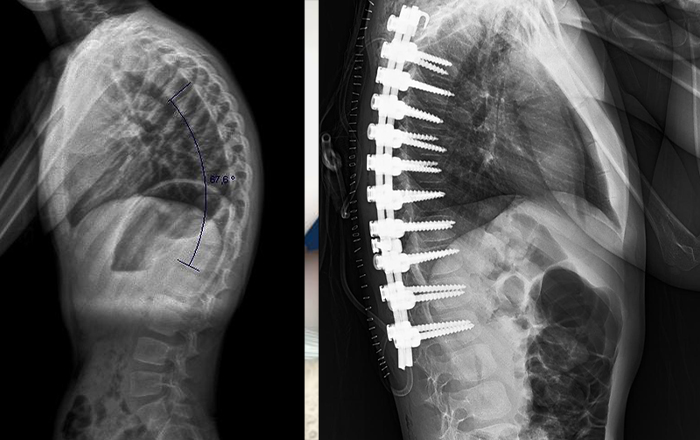

• Skolyoz ve kifoz

• Radyografi (X-ray)

• Spinal füzyon (kaynak) cerrahisi

• Minimal invaziv omurga cerrahisi